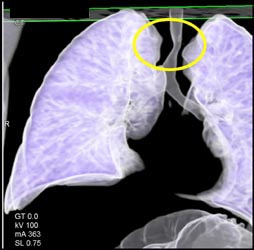

Airway Narrowing Due to Double Arch